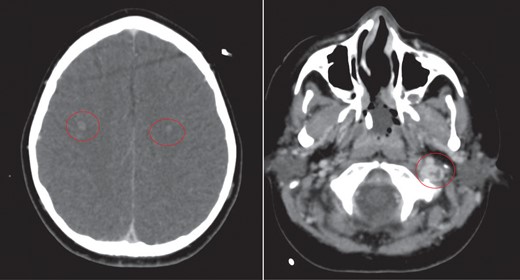

CT of the head with contrast revealed opacification of the left mastoid air cells with multiple ring enhancing abscesses throughout the brain, the largest of which in the left cerebellar hemisphere, measuring 4.4 × 2.9 cm in maximal axial dimensions (Fig. 6). There was non occlusive thrombus of the left internal jugular vein and superior sagittal sinus (Fig. 7). A repeat CT thorax revealed persisting left lung abscesses, a left sided collection and a new post drainage large, right-sided haemothorax.

The largest ring enhancing lesion was within the left cerebellar hemisphere. This was drained surgically.

CT scan of head with contrast revealed multiple ring enhancing lesions within the brain, opacification of the left mastoid air cells and thrombus within the superior sagittal sinus and left internal jugular vein.